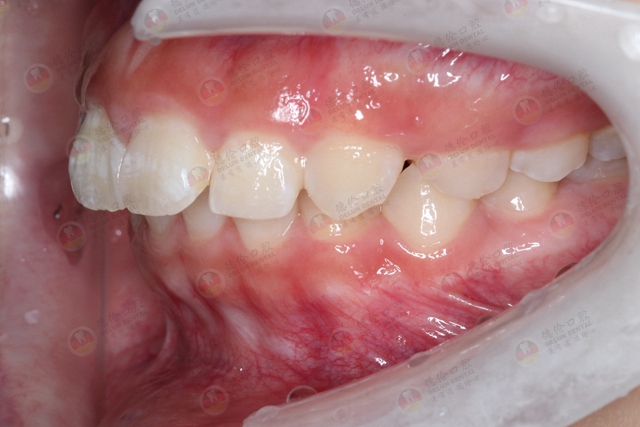

牙齿错颌畸形有多种不同的表现情况,一般分为3类:

1、中性错颌:

多表现为牙列拥挤、牙齿散在缝隙、双颌前突等。

2、远中错颌:

常表现为嘴突、龅牙,或者下颌后缩。

3、近中错颌:常表现为前牙反颌、地包天。

自身存在以上的牙齿错颌畸形的情况,可以考虑通过牙齿矫正的形式改善,同时牙齿存在错颌畸形的情况,会对脸型造成影响,自身有改善容貌的需求,可以通过牙齿矫正来进行改善。